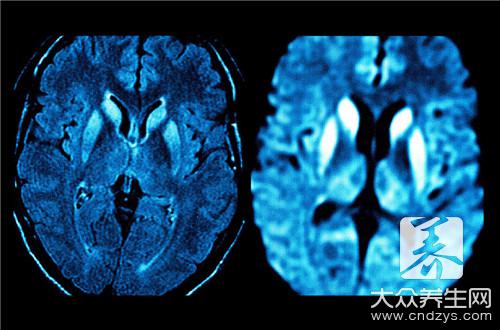

3.磁共振成像

MRI能提供清晰的解剖背景图像,特别是头部图像不受颅后窝伪迹的干扰,有鲜明的脑灰、白质反差,可作冠状、矢状及轴位层面的断层,比CT更为优越。用顺磁性物质钆(Gd)的化合物(Gd-DTPA)作静脉注射,可使组织的T-1弛豫时间明显缩短,因此可作为增强剂来增加病变与正常脑组织之间的对比度,提高MRI的分辨率。目前已普遍认为对神经系统病变的诊断应首选MRI。